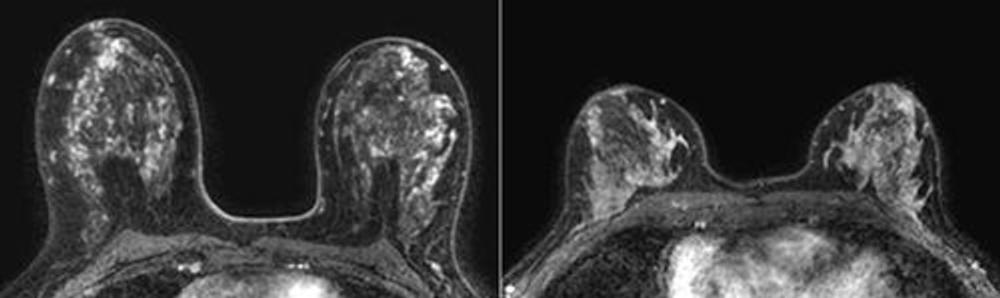

Figure 4. Representative transverse dynamic contrast-enhanced MRI scans in patients in the low and high tertiles of volume of enhancing parenchyma. Please note differences in high and low volumes of enhancing parenchyma are not visible to the naked eye on MRI scans. Left: Baseline MRI scan in a 50-year-old woman with a body mass index (BMI) of 23 and marked background parenchymal enhancement (BPE) who was stratified into the high tertile of volume of enhancing parenchyma. Cancer was detected with MRI in the second screening round. Right: Baseline MRI scan in a 51-year-old woman with a BMI of 24 and marked BPE who was stratified into the low tertile of volume of enhancing parenchyma. No cancer was detected during 6 years of follow-up.